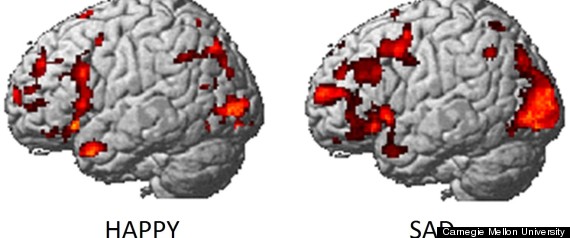

Inside The Emotional Brain

Scientists have found a way to determine what emotions you’re feeling by looking at brain activity measured by imaging technology.

The findings, published in the journal PLOS ONE, are important to emotion research because they bring “a new method with potential to identify emotions without relying on people’s ability to self-report,” study researcher Karim Kassam, an assistant professor of social and decision sciences at Carnegie Mellon University, said in a statement.

For the study, researchers used a combination of brain imaging — functional magnetic resonance imaging — and machine learning. They recruited 10 actors from the university’s drama school to act out different emotions, such as anger, happiness, pride and shame, while inside an fMRI scanner, for multiple times in random order.

To make sure that researchers were able to measure the actual emotions and not just the acting out of emotions, they had the study participants also look at emotion-eliciting images while undergoing FMRI brain scans.

“Despite manifest differences between people’s psychology, different people tend to neurally encode emotions in remarkably similar ways,” study researcher Amanda Markey, a graduate student in the Department of Social and Decision Sciences at the university, said in a statement.